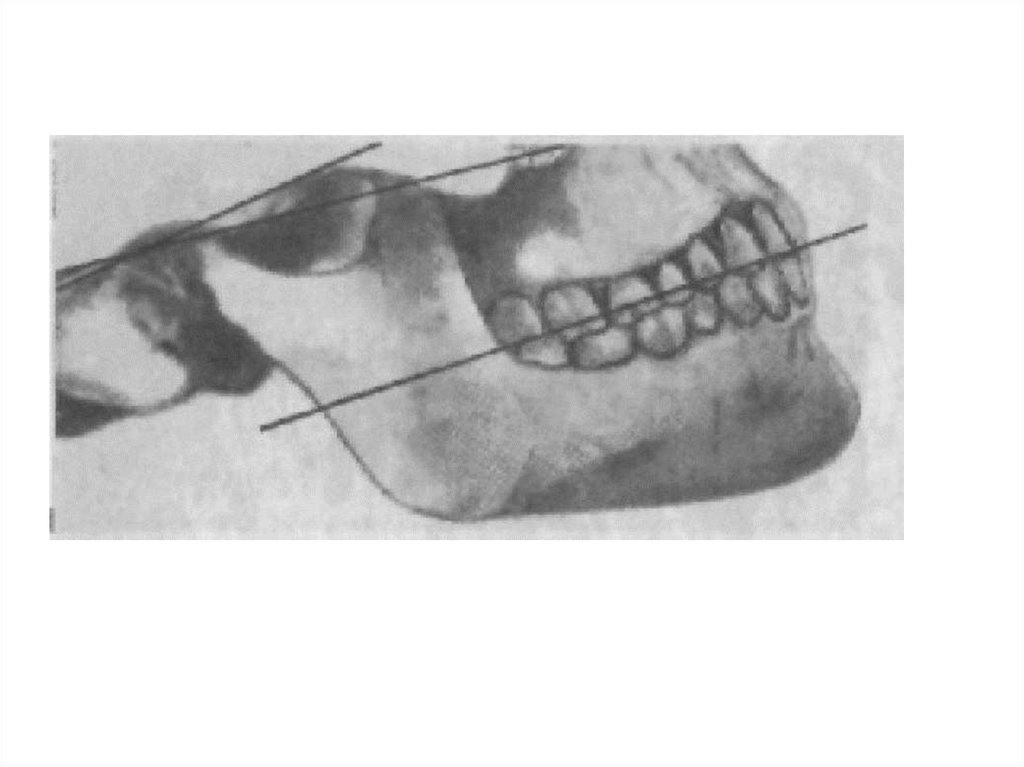

окклюзионная плоскость проходит через

жевательные площадки и режущие края зубов.

(от режущего края центрального резца нижней

челюсти к вершине дистального щечного бугра

второго (третьего) моляра)

9. Протетическая плоскость - это плоскость, воссоздаваемая при протезировании после потери зубов. В боковом участке - проходит по

линии Кампера

( камперовской горизонтали или носо-ушной линии).

Она проецируется на лице от основания крыла носа

до середины козелка уха.

В переднем участке - параллельно зрачковой

линии.

Отдельные авторы эти два понятия «окклюзионная

плоскость» и «протетическая плоскость» считают

аналогами.